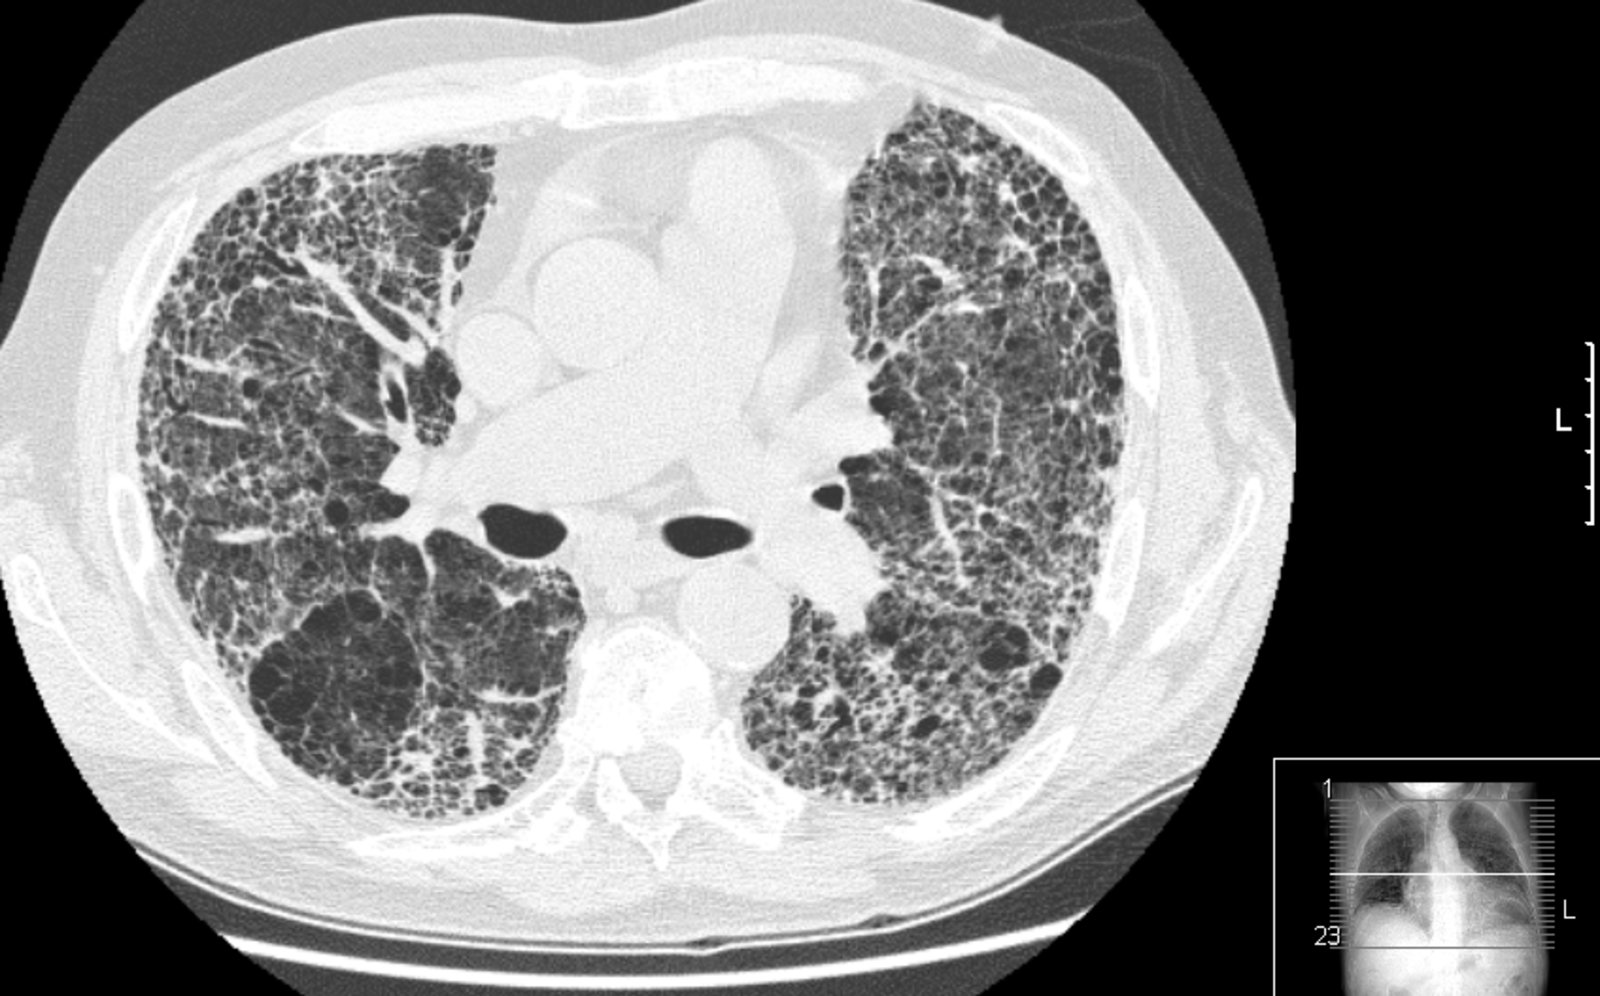

• Restrictive pulmonary disease

• Due to decreased mobility of the thoracic spine and costovertebral joints

• Secondary to apical pulmonary fibrosis or more widespread interstitial lung disease [6]

Restrictive lung disease

• Dyspnea

• Limited chest expansion

• Fine crackles on auscultation

• Pulmonary function testing: restrictive disease pattern

• HRCT [6]

• Ankylosis of costosternal and costovertebral joints

• Apical (upper lobe) fibrosis

• Interstitial lung disease

• Restricted chest expansion and spine mobility → breathing difficulties

• Lungs: fibrosis of upper lobes (apical fibrosis) [6]